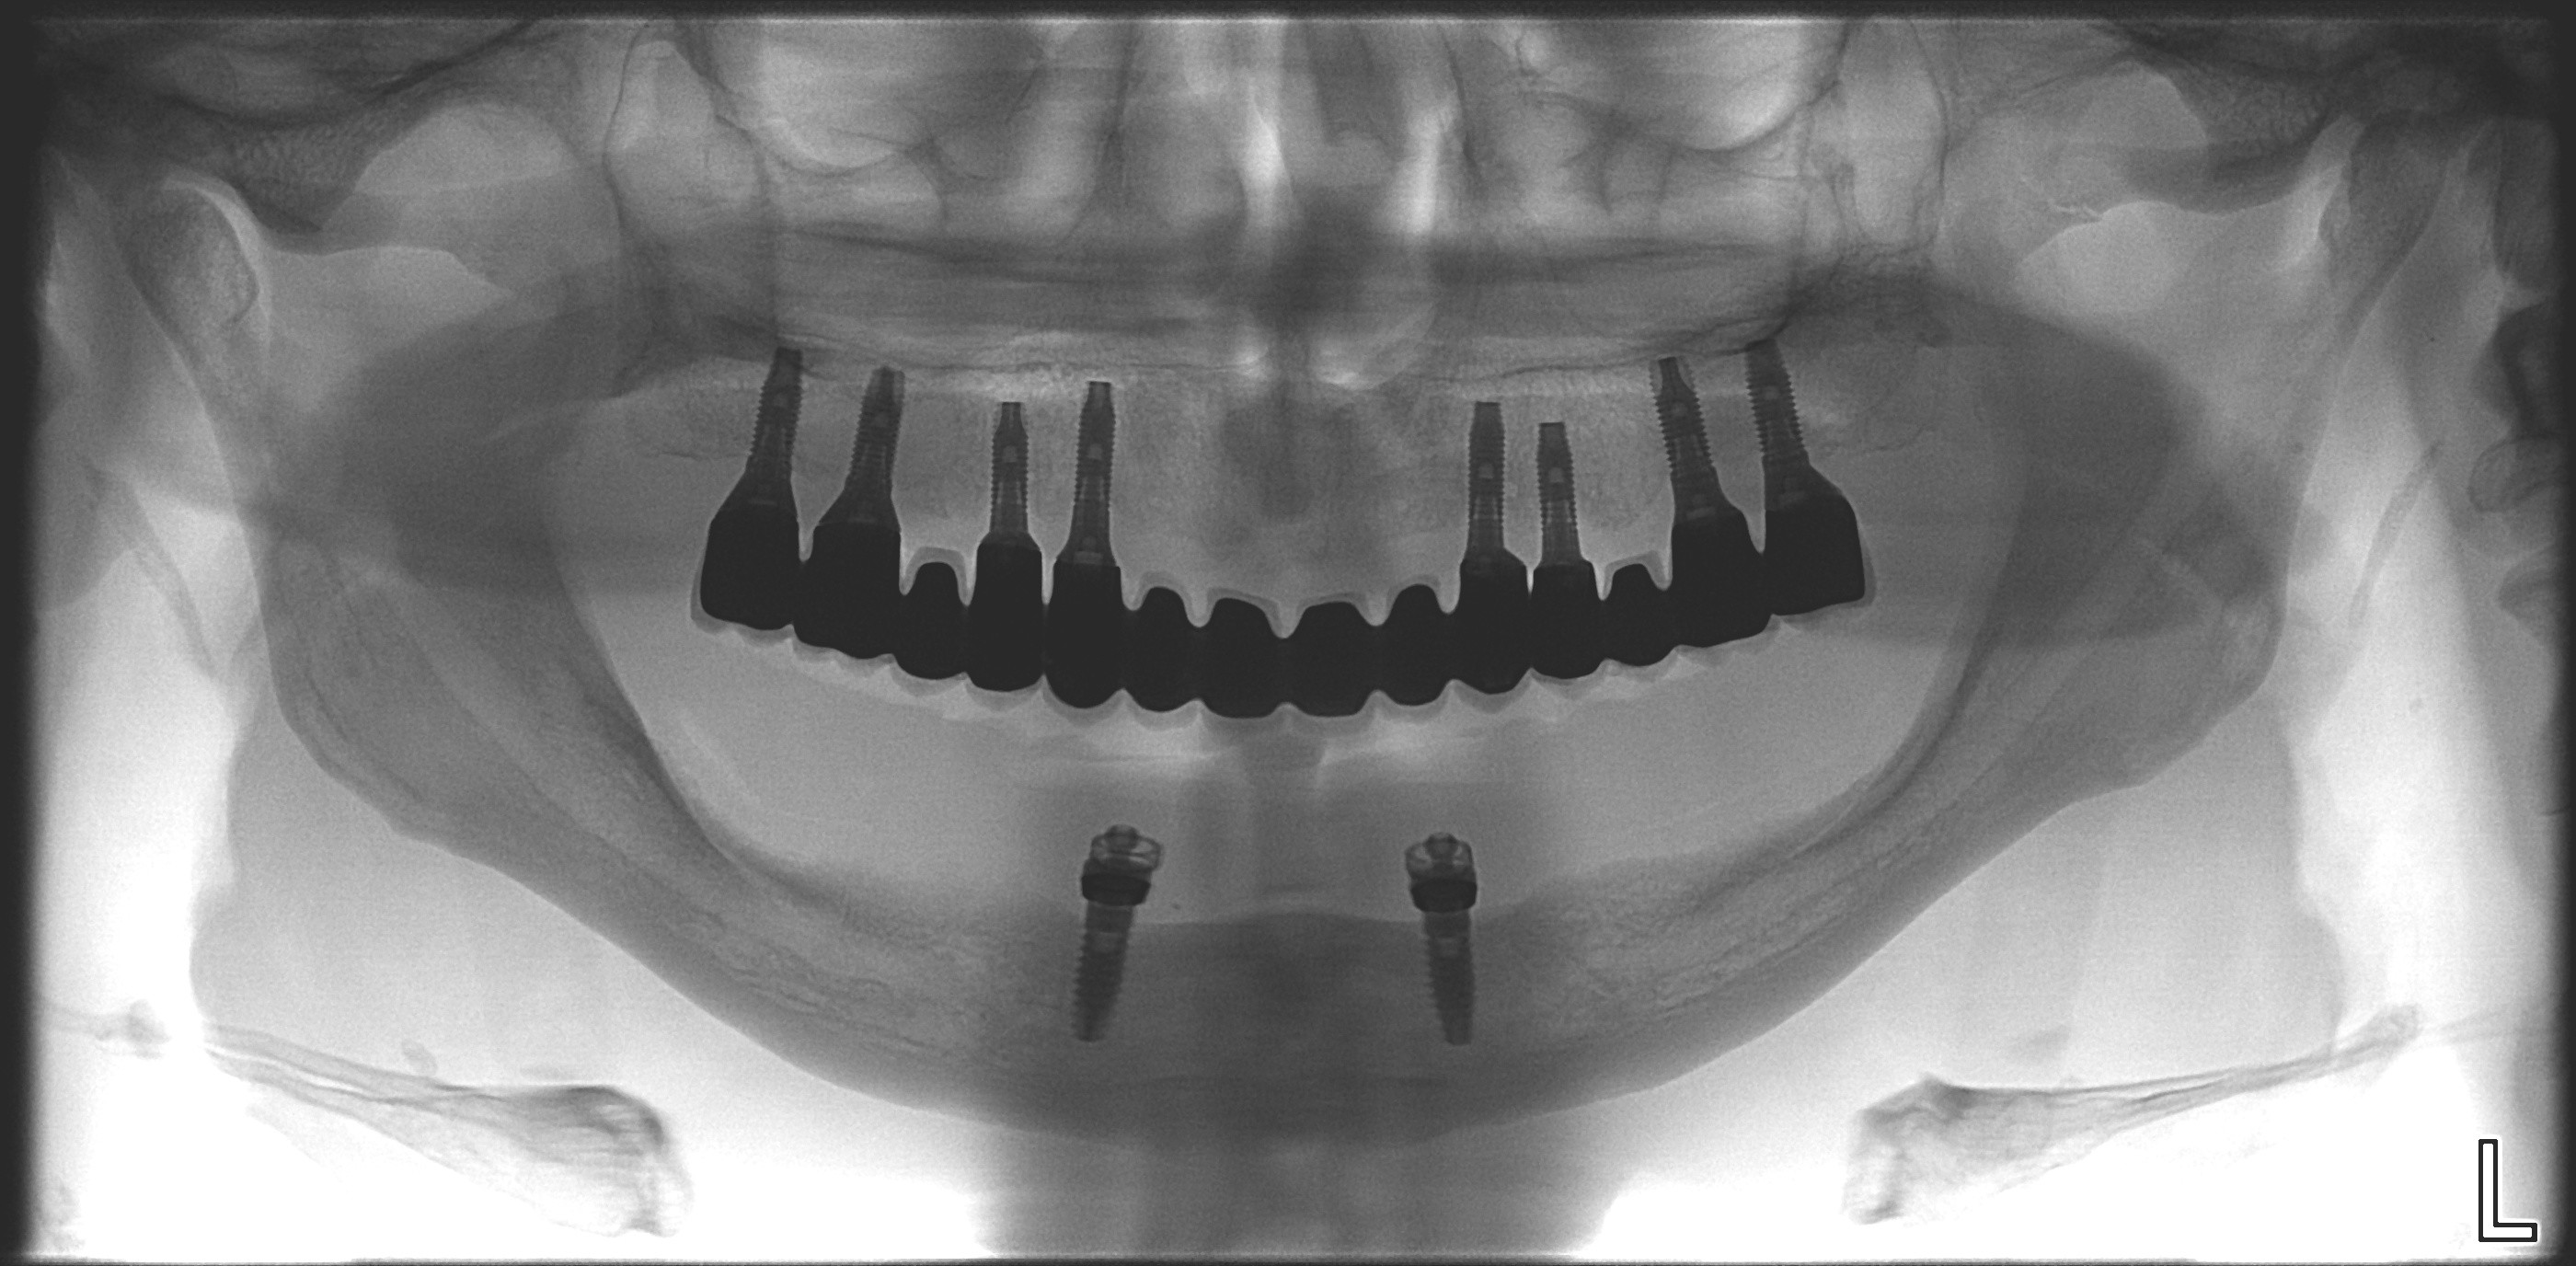

Dès la première consultation, une imagerie globale est réalisée. Un Cone Beam 3D (CBCT) uniquement dédié à l’implantologie est à la disposition des patients. La technique de reconstitution d’image par Cone Beam 3D garantit une réelle qualité d’imagerie des tissus durs, ainsi qu’une irradiation minimale (par acquisition de coupes axiales de 0,15mm).

Une visualisation interactive des données est permise grâce à l’affichage des différentes coupes axiales, para-sagittales et panoramiques ainsi que des objets 3D reconstitués.

Ceci nous permet une validation précise des structures anatomiques, l’intégration du projet prothétique, la simulation des chirurgies à mettre en œuvre et la création des guides chirurgicaux par stéréolithographie.